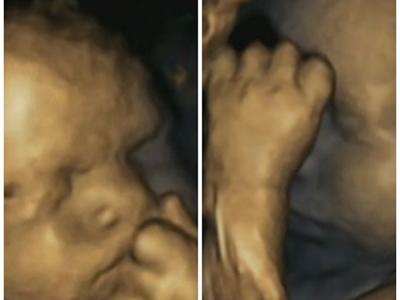

英国研究证胎儿能感应母亲负面情绪

4D扫瞄图片发现母亲发愁时,胎儿摸脸的次数也增加。 (神秘的地球报道)传统智慧...